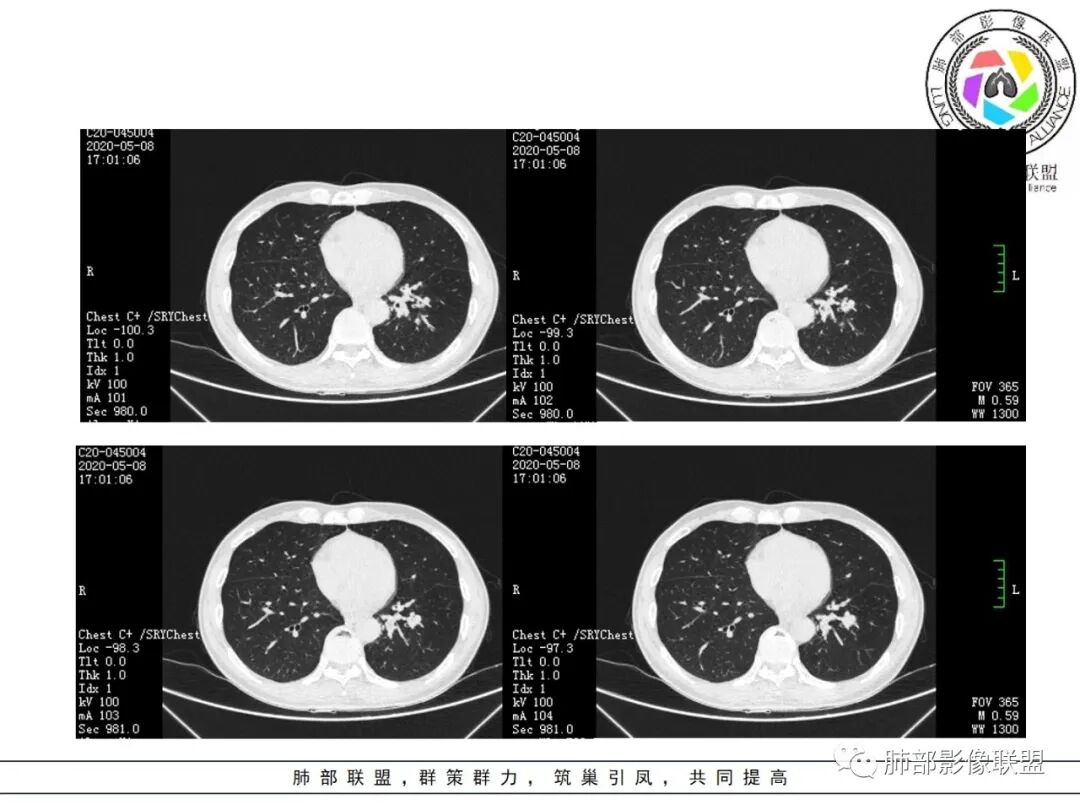

1.关于病灶分布:本例多发小片影局限在左肺下叶,其他肺叶未见异常病灶。

2.关于支气管:上述病灶辖区外侧段支气管截断,环壁结节,远端阻塞性肺炎,是肺癌的重要征象。

支气管内膜结核,易导致支气管较长范围壁增厚,管腔不均匀狭窄甚至狭窄后扩张,也会引起远端肺组织相应的改变,如含气不良、液性潴留等,但较少出现树芽征或新旧不等结节影。支气管镜检有助于鉴别。

4.关于临床资料:老年男性,长期吸烟史,肺气肿背景,要警惕鳞癌的可能性。